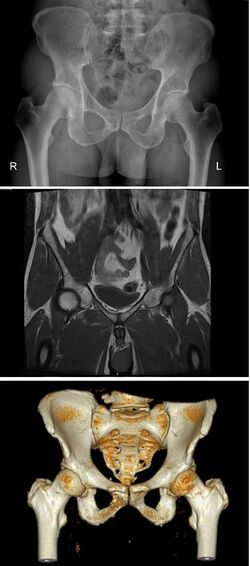

الحوض بالإنجليزية Pelvis ، هو عظم المنطقة من جسم الإنسان التي تسمى (المقعد) أو (المؤخرة). وتكون عند الإناث أكبر منها عند الذكور وذلك لأنها تضم بعض أعضاء الجهاز التناسلي الأنثوي. مثل الرحم ، المهبل، المبيض، قناة فالوب، المثانة والمستقيم. ويقع في الجزء السفلي من البطن ويقع بين عظمة الفخذين.

الحوض هو التركيب الهيكلي العظمي الذي يسند الجزء الأسفل من البطن، ويحيط بالمثانة البولية والطرف الأخير للأمعاء الغليظة، إضافةً إلى الأعضاء التناسلية للمرأة التي يتميز عظم حوضها بأنه أكثر تسطحًا وأعرض من حوض الرجل، كما يتميز فراغه المركزي بالاتساع.

ويتصل العمود الفقري مع الحوض عند المفاصل العجزية الحرقفية. كما تتصل عظام الفخذ بالجزء الأسفل من الحوض بمفاصل كبيرة من مفصلي الخاصرة، ذات تكوين كعبري مدور داخل فراغ حُقِّي مفرّغ، مما يساعد الأرجل على الحركة في عدة اتجاهات. وتقوم كتل من العضلات الكبيرة بتوصيل الحوض بعظام الفخذ. ويتشكل الحوض من جزءين متناظرين من عظام كبيرةٍ هي عظام الخاصرة التي تلتقي في مقدم الحوض لتكوّن الارتفاق العاني، كما تلتحم من الخلف مع (عظمة الإسك) ـ وهي خمس فقراتٍ عظميّة تشكل قطعةً واحدةً من العظام. وتبدو عظام الخاصرة عند مكتملي النمو كأنها قطعةٌ واحدة، ولكنها تتكون من ثلاثة عظام هي: عظم الحرقفة وعظم الورك وعظم العانة. وتتكامل هذه العظام بعضها مع بعض باكتمال النّمو. وعظم الحرقفة هو العظم العريض المسطح الذي تتحسسه عندما تضع يدك على خاصرتك. وعندما تجلس، يرتكز كثير من وزنك على عظم الورك. وتتكون عظام العانة في شكل قوسين في مقدمة الحوض تتصلان عند الارتفاق.